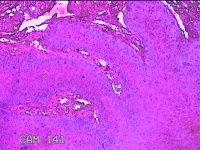

下唇肿物

性别

男

年龄

22岁

临床诊断

口腔黏液腺囊肿

一般病史

下唇肿物一个月余。

标本名称

大体所见

灰白粉红色带皮肤样肿物1x0.3x0.2cm一堆,表面光滑,切开肿物呈实性,切面灰白粉红色,质软。